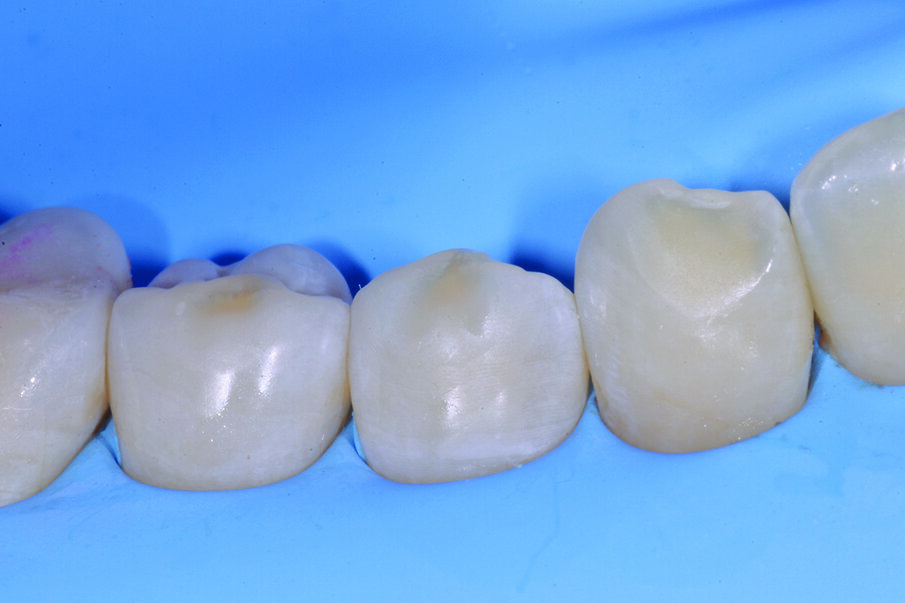

Figg. 2-5_Rimozione dei vecchi restauri presenti su 4.6 e 4.7: gli elementi vengono restaurati con tecnica diretta utilizzando dentina e smalto Enamel Plus HRI Bio Function.

Figg. 6-9_Le superfici occlusali erose e/o abrase vengono ricostruite con strati sottili di smalto composito Enamel Plus HRi Bio Function.